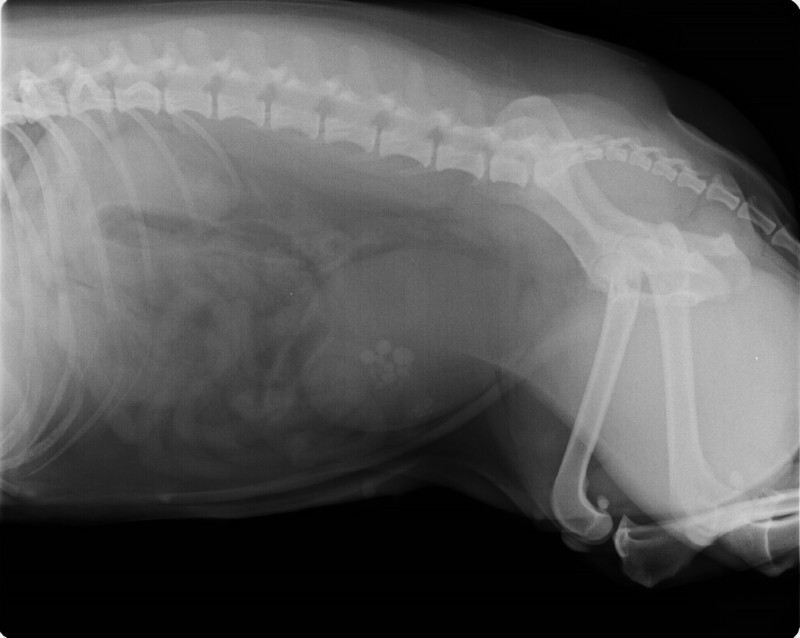

• Abdominalchirurgie